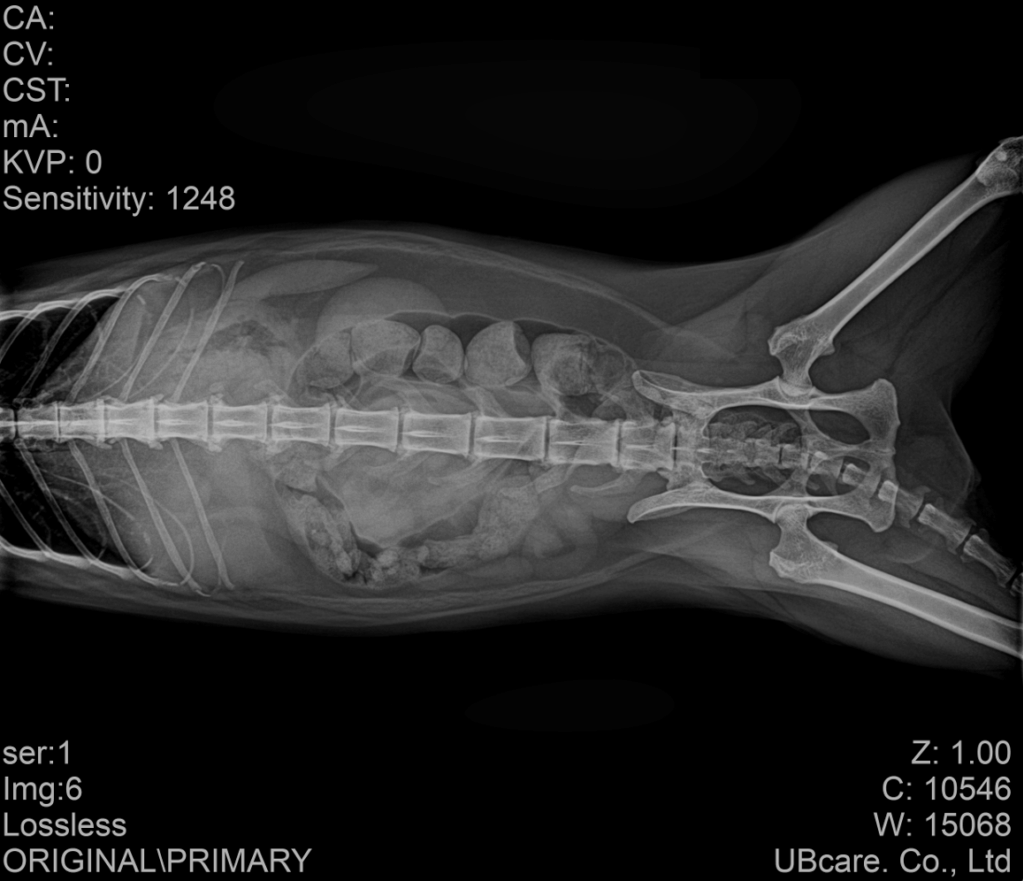

이에 따라 혈액검사와 방사선 검사, 복부 초음파 검사를 포함한 전반적인 평가를 진행하였습니다. 혈액검사에서는 췌장염 지표인 fPL이 양성으로 확인되었고, 간 수치도 함께 증가되어 있었습니다. 방사선 검사에서는 장폐색이나 명확한 이물 소견은 보이지 않았지만 대변 정체가 일부 확인되었습니다.

내원당시 복부방사선검사 결과 / 출처: 강서YD 동물의료센터